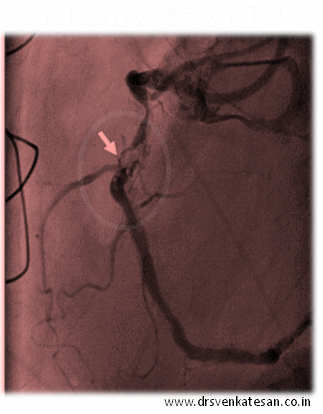

chronic total occlusion cto tips and tricks

While each one of the above factor appears very much important  morphology of the lesion is the  clear winner  ( Which includes , the content of the lesion , hardness , micro channels , thickness of the proximal and distal caps, the length and   tortuosity   of the CTO     ( which is invisible ) the collateral status will ultimately determine the success)

It is becoming increasingly clear  cardiologist expertise is getting less and  less important .

Finally ,  it must  be told to our  younger generation of cardiologists , crossing a  CTO and deploying a stent  is not synonymous with success .It should result in long term sustained distal flow and make a significant impact on the patients symptoms (If at all any !) and survival.